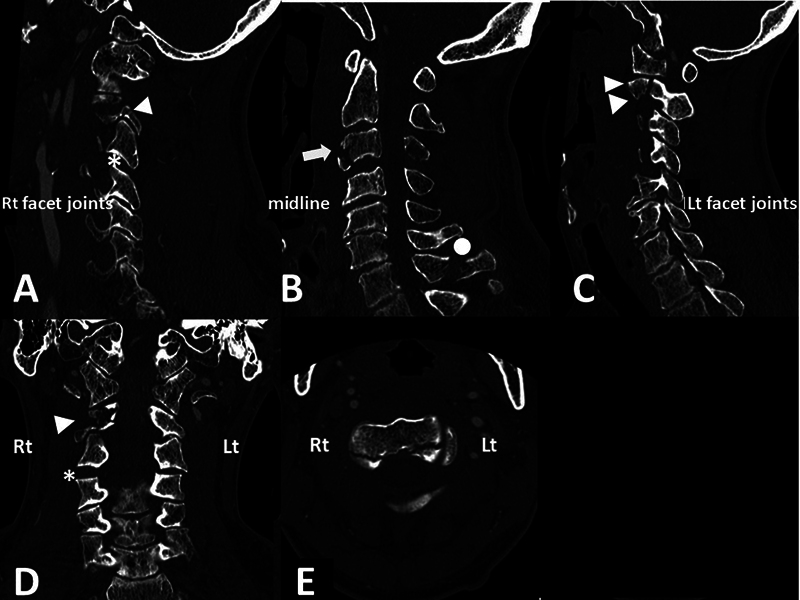

后Ponticulus posticus (PP),也被称为弓形孔,是寰枢椎(C1)的一种解剖变异,是寰枢-枕后膜的骨化,椎动脉(VA) V3段穿过寰枢椎后膜。PP患者在C1侧块内放置多轴螺钉被认为是有风险的,因为可能存在VA损伤的风险。我们报告一例双侧PP,后路固定治疗不稳定的上颈椎损伤。患者,70岁男性,持续跌倒引起的不稳定上颈椎损伤(外伤性C2椎体滑脱伴C3-4小关节单侧脱位)。在最初的保守治疗后,在亚急性期进行了后路固定手术。术前图像显示双侧PP存在。因此,放弃了将螺钉置入C1侧块的原计划,改为将椎板钩置入一侧,将螺钉置入另一侧的C1后弓。他的术后过程很顺利,受伤后27天他被转移到康复医院。在伴有PP的上颈椎不稳病例中,必须根据损伤程度和VA病程逐一考虑固定方法。

Ponticulus posticus (PP), also known as arcuate foramen, is an anatomical variation of the atlas (C1), which is an ossification of the posterior atlanto-occipital membrane and through which the V3 segment of the vertebral artery (VA) runs. Placement of a polyaxial screw in the C1 lateral mass is considered risky in those with PP because of possible risk for VA injury. We report a case with bilateral PP in which posterior fixation for unstable upper cervical spine injury was performed. The patient, a 70-year-old man, sustained a fall-induced unstable upper cervical spine injury (traumatic C2 spondylolisthesis with unilateral dislocation of the C3-4 facet joint). Following initial conservative treatment, a posterior fixation surgery was performed in the subacute phase. Preoperative images revealed the presence of bilateral PP. Therefore, an original plan to place the screws in the C1 lateral mass was discarded, and instead, placement of the laminar hook on one side and placement of the screw into the C1 posterior arch on the other side was performed. His postoperative course was uneventful, and he was transferred to a rehabilitation hospital 27 days after the injury. In cases of upper cervical spine instability with concomitant PP, it is essential to consider the fixation method based on the extent of the injury and the course of the VA on a case-by-case basis.